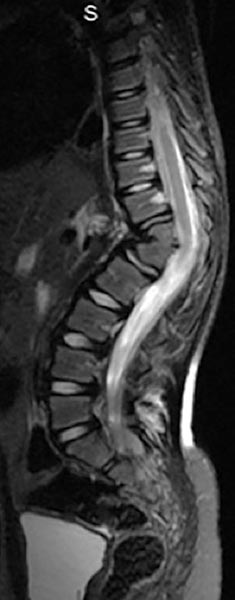

Ressonância magnética é fundamental para diagnosticar alterações cerebrais, na medula espinhal ou nervos que possivelmente podem estar associados. Entre eles se destaca: malformação de Chiari (anormalidade do cérebro que é deslocado caudalmente ao espaço reservado para medula espinal), siringomielia (fluxo anormal de liquor criando uma bolsa no interior da medula espinal), diastematomielia (segmentações na medula espinal), medula presa (junção anormal da medula na base do saco dural)1,6 (exemplo figura 5).

Figura 5. RM demonstrando deformidade devido escoliose congênita